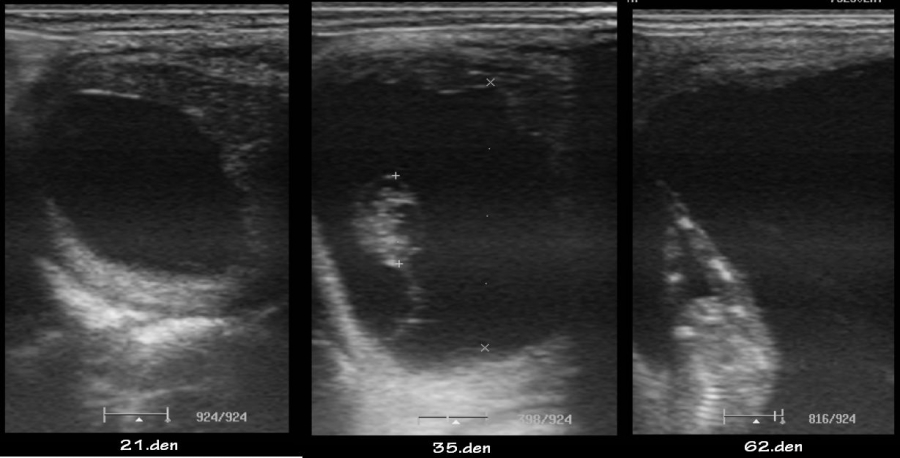

Vývoj embrya u jedné klisny

embryo kolem 21.dne

Embryo 31. den